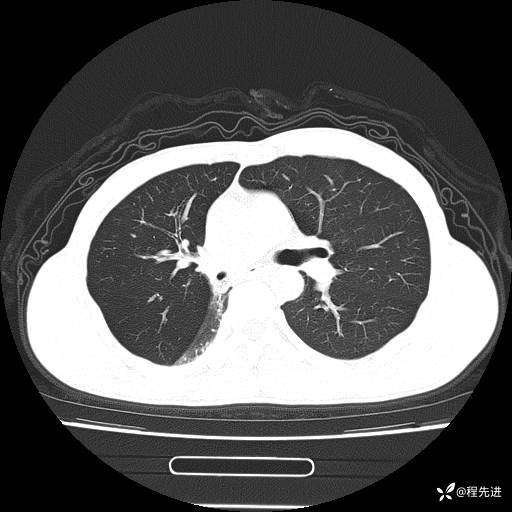

患者性别:男

患者年龄:49岁

主诉:咳嗽、胸痛1周

简要病史:1周前受凉感冒后开始出现咳嗽症状,阵发性连声咳,痰多,黄白痰,不易咳出,伴胸痛、气紧、胸闷,右侧为主,活动用力、呼吸时胸痛明显,曾在当地诊所贴敷膏药仍疼痛

体格检查:T:36.3 ℃ P:80 次/分 R:20 次/分 BP:120/88 mmHg,指脉氧饱和度97%,意识清晰,呼吸平稳,右侧第二、三肋骨压痛,可见膏药贴敷,皮肤无异常,双肺呼吸音粗,未闻及干湿性啰音。心率80次/分,节律整齐,无杂音。腹平软,全腹无压痛无反跳痛

临床诊断:社区获得性肺炎

CT平扫: